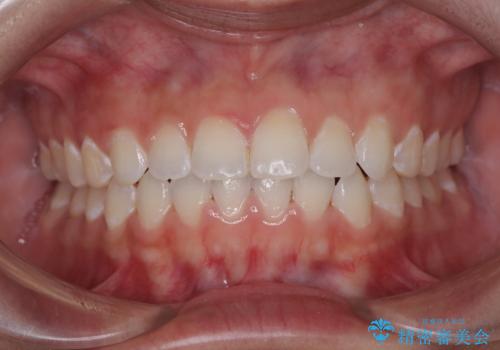

捻れて前に出ている前歯 ワイヤー装置での非抜歯矯正